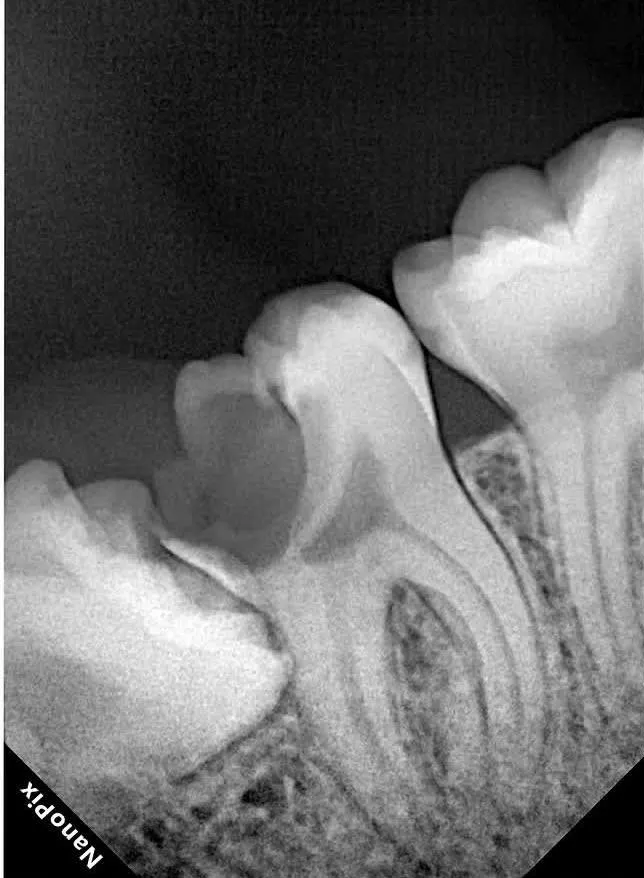

قبل

بعد